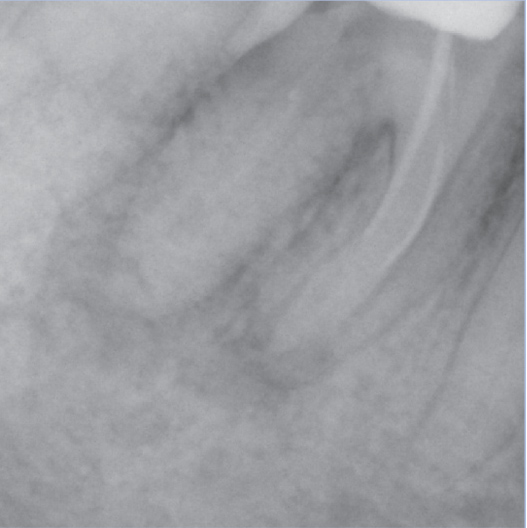

After

After Root Canal treatment